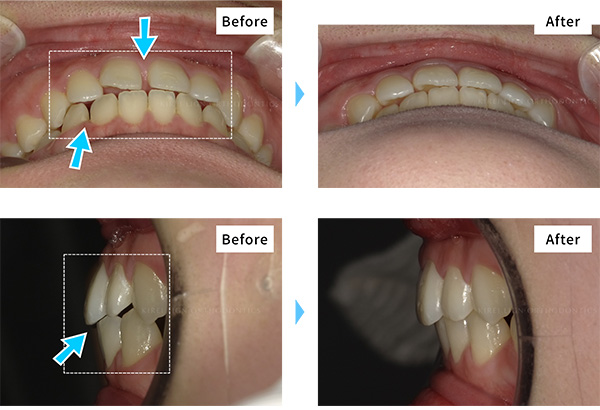

キレイライン矯正で実際に治療した方のビフォーアフター写真・治療費用を紹介します。

自分に近い歯並びを探して、どれくらいの費用で治療できるのか、参考にしてみてください!

【3~4回の症例】

比較的少ない回数で終了した症例です。ご覧のとおり、治療費用を抑えることができています。

-

- 治療期間

- 約6ヶ月(キレイラインを4回実施)

- 治療費用

- 160,000円(税込176,000円)

-

No

47108131

-

症状

出っ歯,ガタガタな歯

-

再診料

(4回) 12,000円 (税込13,200円)

-

追加治療

拡大床(上下)80,000円 (税込88,000円)

- ※効果には個人差があります。※拡大床は、キレイライン矯正による矯正歯科治療の一環ではありません。患者様のご要望や症状により医師の判断のもと行われる「クリニックの治療」に該当しますので、詳細は提携クリニックに直接ご確認ください。